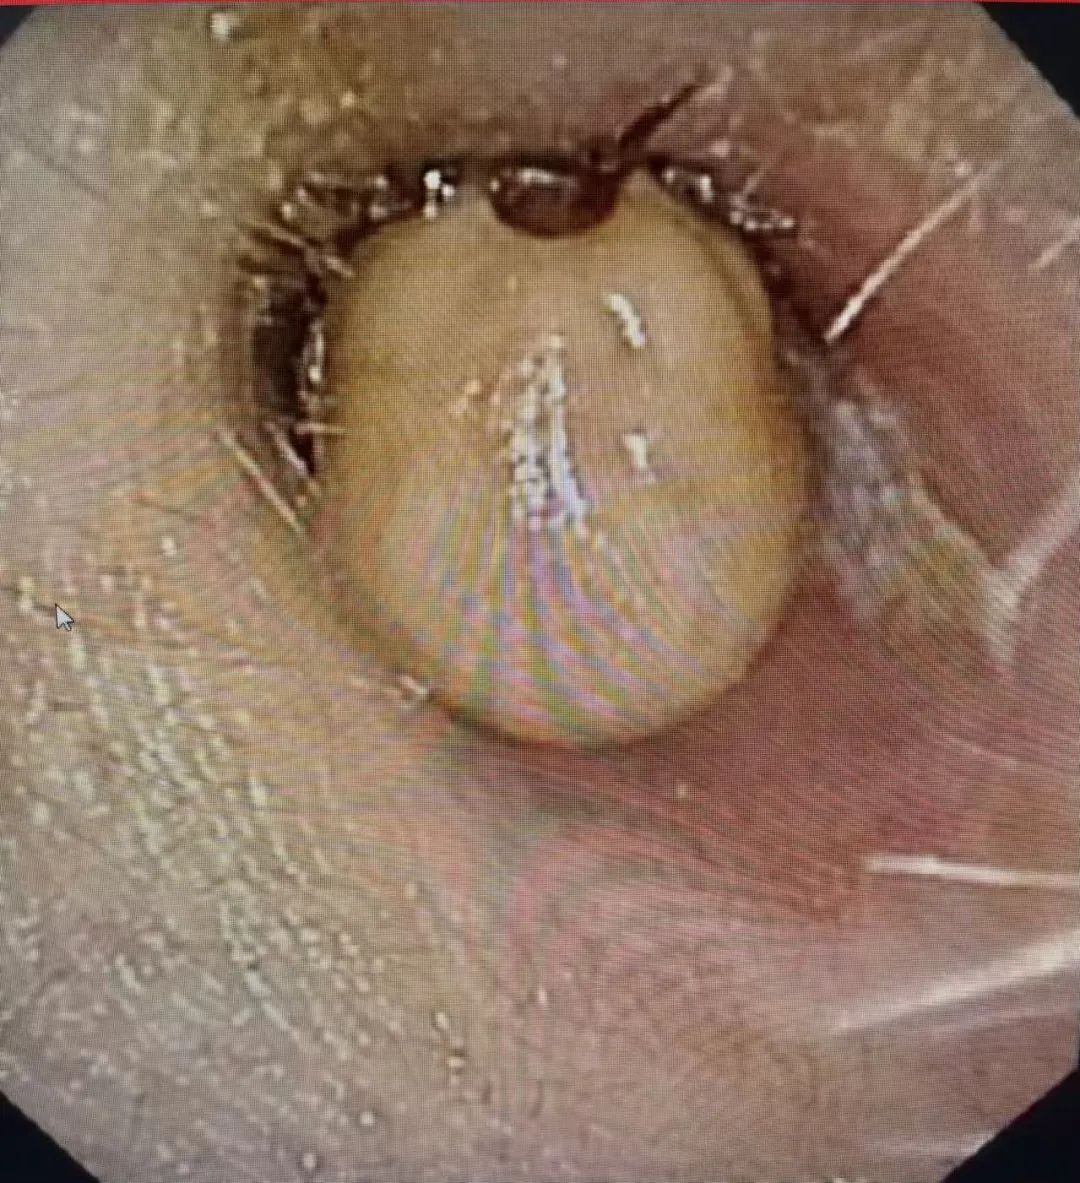

患者一周前曾前往阿尔山旅居,返回乌市后,左侧耳道便出现持续性疼痛、堵塞感。起初,她在当地诊所接受抗生素治疗,然而症状却始终未见缓解。备受折磨的患者来到兴安盟人民医院耳鼻喉科寻求进一步治疗。经专业耳内镜检查后,惊人地发现患者左侧外耳道深处吸附着一只蜱虫!此时的蜱虫已明显饱胀,呈现灰白色,其口器深深刺入外耳道皮肤,周围组织也出现了红肿现象,这便是导致患者耳痛的 “罪魁祸首”。

经过慎重讨论,耳鼻喉科团队当机立断,决定为患者实施全身麻醉下的耳内镜下蜱虫取出术。在全麻状态下,患者肌肉完全放松,无任何体动,为精细操作提供了稳定环境。团队借助高清耳内镜的放大视野,手持精密显微器械,小心翼翼地将蜱虫连同深嵌皮肤的口器一并切除,随后给予碘仿填塞耳道。整个手术过程紧张有序,最终成功将蜱虫完整取出,手术取得圆满成功。